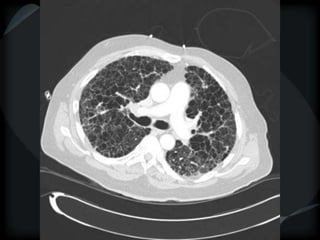

Airspace Patterns

 Diffuse ground-glass

 Patchy consolidation (peripheral)

 Inter and intralobular septal thickening / ground glass/crazy paving

 Reverse halo/atoll sign

 Hogshead cheese sign

 Perilobular pattern

 Organising pneumonia – COP/BOOP

 Chronic eosinophilic pneumonia

 Alveolar proteinosis

 Desquamative interstitial pneumonitis

 Alveolar microlithiasis

 Alveolar sarcoid

 BAC